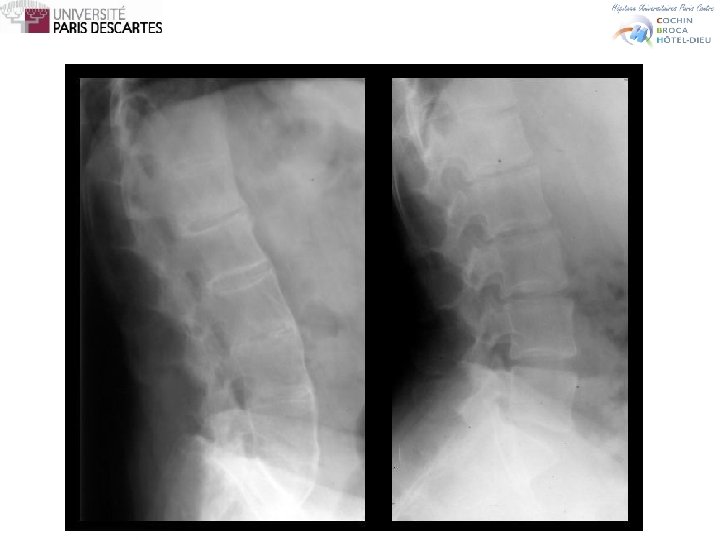

SPONDYLARTHROPATHIES Diagnostic • Lombalgie ≥ 3 mois • Ayant débuté avant 45 ans Sacroiliite +1 signe ou HLA B 27 +2 signes • Lombalgie inflammatoire • Synovite • Enthésite (talalgie) • Uvéite • Dactylite • Psoriasis, entérocolite • Réponse aux AINS • Histoire familiale de Sp. A • HLA B 27 • CRP augmentée

SPONDYLARTHROPATHIES Exemple • Lombalgie chronique inflammatoire • RN, RM • Efficacité des AINS • Uvéite • Psoriasis • Entérocolite • Synovite • Enthésite • CRP • Rx bassin • IRM